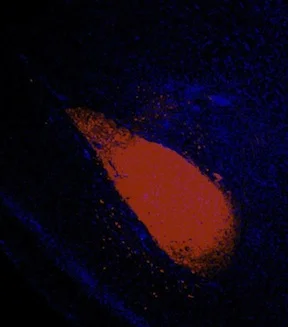

Brainbow